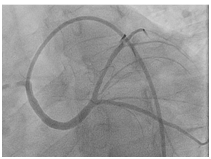

38 year old male patient with 15 packs per year smoking history presented to a peripheral hospital with acute onset typical chest pain for 30 minutes. His ECG revealed ST- Elevation acute lateral wall myocardial infarction. He was thrombolyzed with t-PA with complete resolution of his ECG changes. Echocardiogram showed mild LV dysfunction with LVEF of 45% and lateral wall hypo kinesis. He was then transferred to our center where he was taken to the catheterization laboratory and diagnostic coronary angiogram was done following obtaining an informed consent. It was difficult to engage the left coronary artery with Judking left catheter. A right judkins was taken to visualize the right coronary system. This revealed that the right coronary artery to be free of disease (Figure 1) and the left coronary artery to originate from the right coronary sinus. The anomalous left main showed a mid-shaft hazy and eccentric lesion (Figure 2), Normal left anterior descending and normal left circumflex. The patient was discussed in a heart team meeting and it was decided to obtain coronary CT angiogram to define the course of the anomalous left coronary artery which was retro-aortic (Figure 3). The patient was offered bypass surgery of which he declined to accept. The patient informed decision was to opt for PCI. A straight forward intervention was carried out using Judging’s 4 guiding catheter, which easily incubated the anomalous left main a BMW wire easily passed to the distal LAD and a direct 4.0x22 mm resolute stent deployed (Figure 4). A second stent 4.0x8 mm resolute stent deployed proximally to cover an area of plaque shift. A final IVUS was done which showed well stent apposition (Figure 5). The procedure was supplanted with 300mg of Plavix and 7000 unit of heparin. He was discharged next day.

Figure 1 Coronary angiography showing right and left coronary arteries originating from the right cornary sinus of Valsalva.